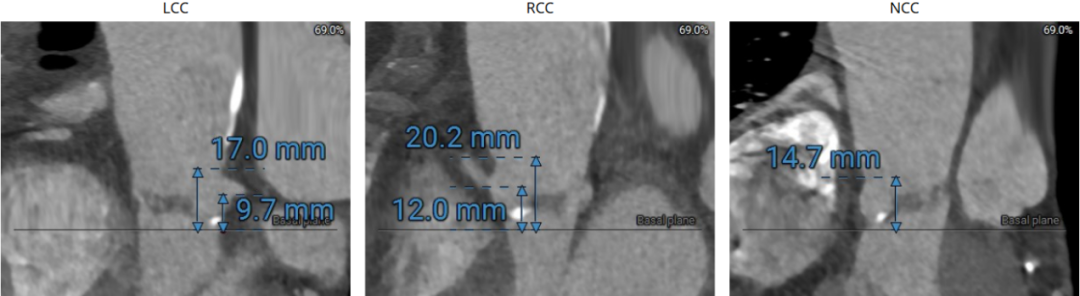

1、冠脉开口低,同时瓣叶增厚增长,导致冠脉风险高;

患者冠脉存在狭窄,TAVR术前首先进行冠脉处理。由于患者主动脉根部结构较小,左冠开口低,合并瓣叶增厚增长,植入人工瓣膜将存在冠脉阻塞风险,造成严重的手术并发症。经过分析讨论,术者决定瓣膜植入前对左侧冠脉进行预保护。